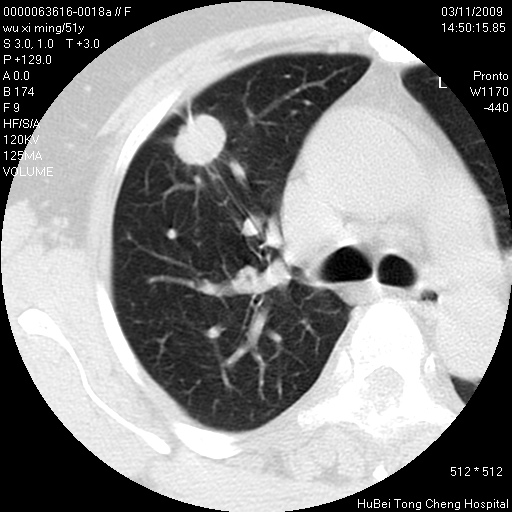

患者 女,51岁。因“胆囊炎,胆囊结石”,行常规术前胸部x线检查发现:右上肺结节病灶,建议行进一步检查。患者无咳嗽、咳痰及咯血等呼吸道症状,近期出现背部疼痛不适。

胸部ct轴位平扫(层厚10mm,螺距1.5,重建间隔10mm;部分层面:层厚3mm,螺距1.0,重建间隔3mm),图像如下:

1、周围型肺癌。(毛刺正、血管束集征,分叶。)

集束征,胸膜牽拉征,毛刺,淺分葉高度提示ca.

右肺周围型肺癌伴肺内转移及胸椎转移。已无手术机会。